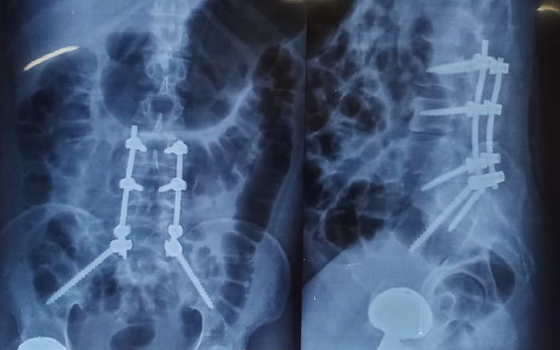

Dr. Somashekar D is an experienced spine surgeon in Bangalore. He is currently practising as a Consultant - Spine Surgery at Manipal Hospital Jayanagar, Bangalore. With nearly 10+ years of expertise in spine care, Dr. Somashekar has established himself as a highly skilled spine surgeon, contributing to over 1,500+ spine surgeries independently, ranging from simple decompressions to complex spinal reconstructions. His practice is deeply rooted in precision-based techniques and evidence-guided clinical protocols, ensuring both safety and long-term functional outcomes for his patients. He is a top spine surgeon in Jayanagar.

We offer comprehensive treatment for spine issues that is on par with any leading spine center worldwide. Our services encompass both non-surgical and surgical treatments tailored to address your specific condition. Our expertise covers a wide range of spine surgeries, including minimally invasive spine surgery, cervical spine surgery, scoliosis surgery, and complex spine surgeries.

Covers a wide range of spine surgeries, including complex spine surgeries.